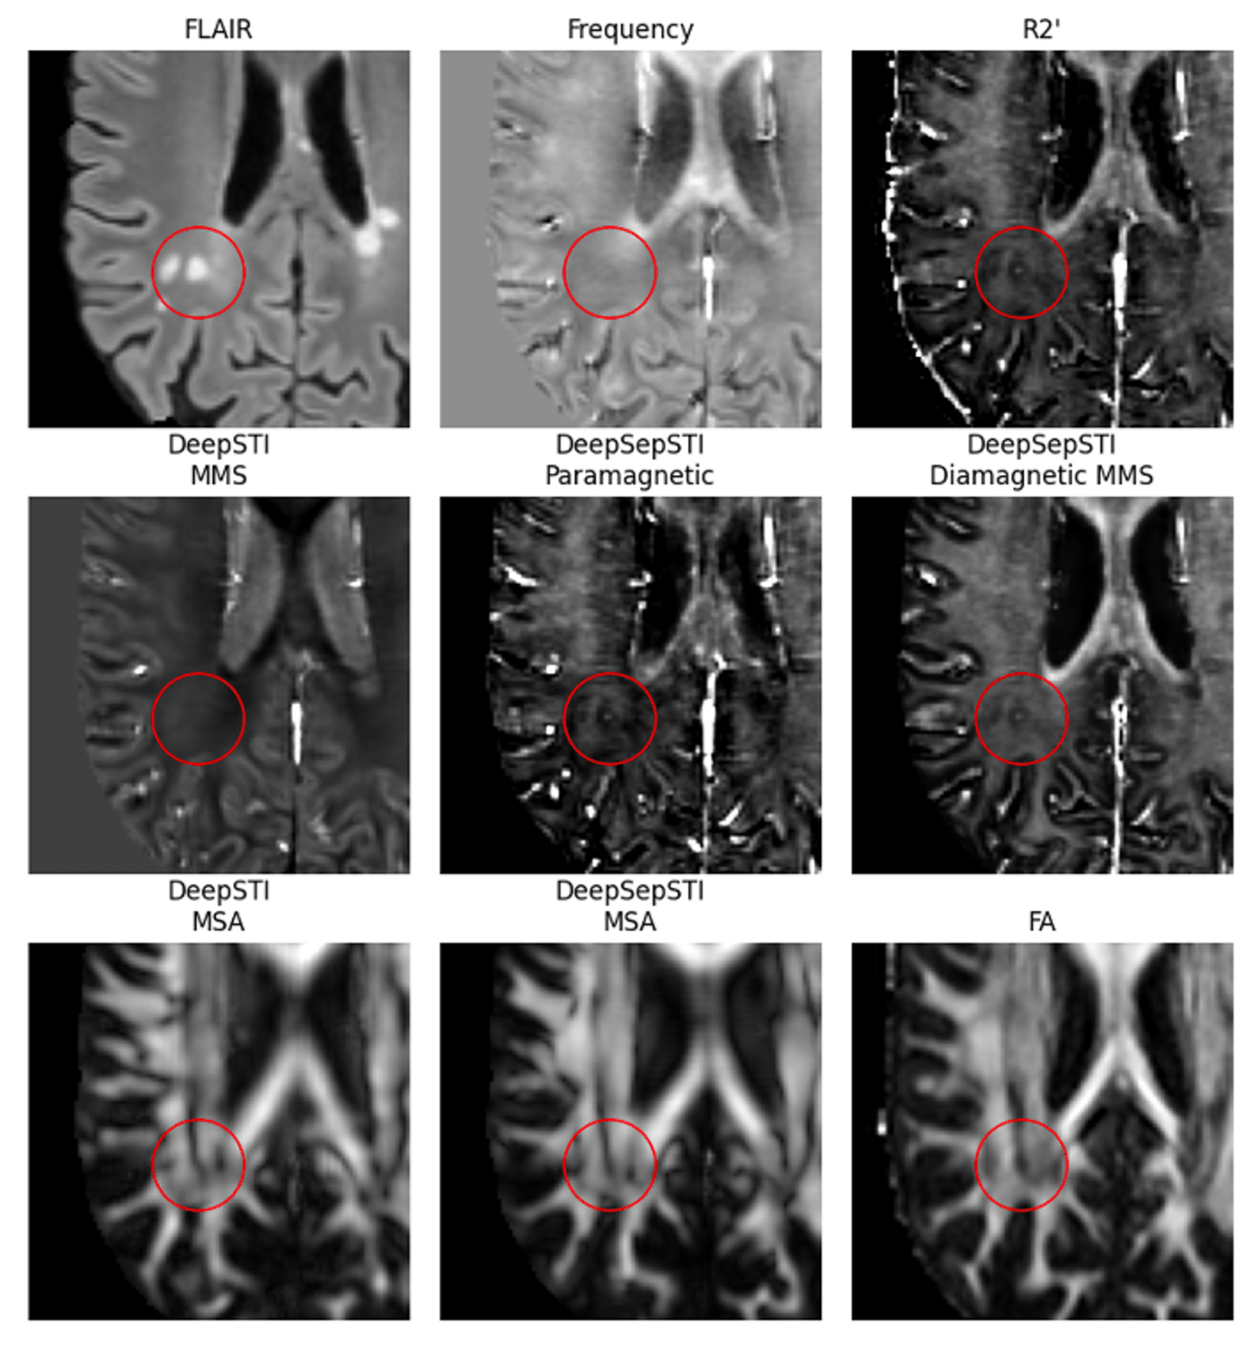

Susceptibility Source Separation: WaveSep and DeepSepSTI

In vivo Quantitative Susceptibility Mapping (QSM) Separation Result from WaveSep

In vivo STI Separation Result from DeepSepSTI on a Multiple Sclerosis Patient

- WaveSep: decouple susceptibility estimation and source separation

- DeepSepSTI: joint susceptibility estimation and source separation